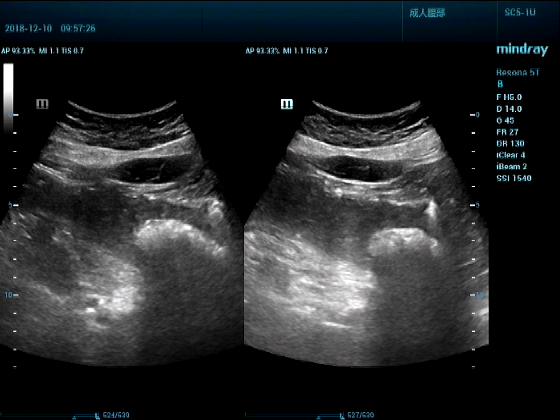

病例一:女,53岁,胃部不适一周来诊

超声可见:胃腔内见一小鸡蛋大强回声团块,后方伴强声影,位置活动。

问及病史吃山楂,柿子。

超声提示:结合临床考虑胃结石,治疗后复查